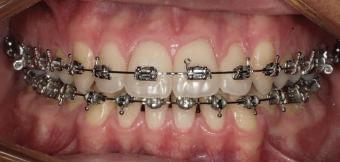

20 Dental Tribune Bulgarian Edition / октомври 2022 г. П ациентите със завършен растеж и скелетни проблеми обикновено представляват предизвикателство за ортодонт ската практика. Необходимостта от изваждане на зъби в комбинация с особеностите на възрастовата ортодонтия изисква особено внима ние. Фокусът върху критично важното значение на позицията на долните резци във връзка с дългосроч ната стабилност и постигането на оптимални оклузални взаимоотношения при затварянето на екстракционните пространства лесно може да излезе извън контрол. Когато към тези чисто кли нични проблеми се добави и стресът от натоваре ната практика, предизвикателството става още по-голямо. Всички тези фактори налагат използ ването на доказан подход с ясни и последовател ни стъпки, в което се разкрива силата на дисциплината „Алекзандър“ – предвидим протокол през целия процес на елиминиране на ротациите, ниве лиране на дъгите, затваряне на екстракционните пространства и финализиране на случая. Именно такъв е и случаят, който презентираме –екстракционен, скелетен клас 3 при възрастен па циент, лекуван по системата „Алекзандър“. ПРЕДВИДИМИ РЕЗУЛТАТИ ПРИ ПАЦИЕНТИ СЪС ЗАВЪРШЕН РАСТЕЖ И СКЕЛЕТЕН КЛАС 3, ИЗПОЛЗВАЙКИ ЕКСТРАКЦИОННО ЛЕЧЕНИЕ ПО ДИСЦИПЛИНАТА „АЛЕКЗАНДЪР“ Д-р Радой Димитров, България Преди започване на лечение клиничен случай | ортодонтия Фиг. 1а–1e Преди започване на лечение. Пациентът пристига в практиката с основното оплакване от невъзмож ност за нормално дъвчене. Снета е цялата необходима диагностична ин формация. Фиг. 1f–1h Снимки в профил и анфас. Фиг. 1i–1k Панорамна снимка, телерентгенография и анализ на телерент генография. Фиг. 1а Фиг. 1d Фиг. 1f Фиг. 1g Фиг. 1h Фиг. 1e Фиг. 1b Фиг. 1c Фиг. 1i Фиг. 1j Фиг. 1k

closed.

21Dental Tribune Bulgarian Edition / октомври 2022 г. ДИАГНОСТИЧНИ РЕЗУЛТАТИ: 1. Възраст на пациента: 21 години 2. Скелетен клас III (ANB 0) 3. Зъбен клас 3 4. Ръбцова захапка във фронта, кръстосана в дисталните участъци 5. Тясна горна челюст 6. Overjet – 0 мм, Overbite – 0 мм 7. Несъответствие на горната с долната средна линия 8. Единични контакти в ЦО 9. Хиподивергентен тип на растеж SN/MP – 33.5 10. Неравен гингивален контур 11. Неравна линия на усмивката 12. Тенденция за рецесии в долен фронт ПРЕПОРЪЧИТЕЛНО ЛЕЧЕНИЕ: Пълно ортодонтско лечение с метални брекети „Алекзандър“ Корекция на клас 3 захапката в областта на кучешките зъби с екстракция на първите пре молари в долна челюст Корекция на кръстосаната захапка в дистални участъци Коригиране на ръбцовата захапка във фронта Подобряване на ОJ и OB на пациента Стрипинг в долен фронт Подреждане на зъбите в горната и долната челюст Професионално хигиенизиране и профилактични дентални прегледи са препоръчителни на всеки 6 месеца. 1-ви месец След 1 месец са залепени брекети в горната челюст – поставена е еластична дъга. 016 NiTi. В долната челюст са елиминирани ротациите, поставена е стоманена дъга. 016SS, закалена с ток, и еластична верижка за затваряне на пространствата. 3-ти месец В долната челюст е поставена трета дъга – 17 x 25 NiTi с къси лигатури и верижка

В горната челюст се затварят пространствата с дъга .016SS и верижка. 5-и месец На 5-ия месец след залепяне на брекетите в долната челюст е поставена стоманена дъга 16 x 22 SS с четвъртито сечение, омега луп и тай бек. В горната челюст е поставена дъга 17 x 25 NiTi. Поради липсата на стабилни оклузални контакти са поставени лингвални верижки в областта на моларите, за да се предотврати нежелана ротация на 7-ите зъби. 6-и месец На 6-ия месец от началото на лечението са екстрахирани долните първи премолари, поставена е дъга 16 x 22 SS със затваряща чупка teardrop. Чупката се активира всеки месец по 1 мм с чинч-бек. клиничен случай | ортодонтия СТЪПКИ НА ЛЕЧЕНИЕТО Начало на лечението Лечението започва с поставяне на апарат за бърза експанзия в горната челюст. През първия месец от лечението са направени 24 оборота на апарата за експанзия. Залепени са брекети в долната челюст, поставена е дъга 17x25 CuNiTi, като са предпи сани клас 3 ластици (1/4”,4 1/2 oz) по време на сън, за да се осигури контрол върху торка на долните резци. Фиг. 2а Фиг. 3a Фиг. 4a Фиг. 3b Фиг. 4b Фиг. 3c Фиг. 4c Фиг. 3d Фиг. 4d Фиг. 3e Фиг. 4e Фиг. 5a Фиг. 5b Фиг. 5c Фиг. 5d Фиг. 5e Фиг. 6a Фиг. 6b Фиг. 6c Фиг. 6d Фиг. 6e Фиг. 7a Фиг. 7b Фиг. 7c Фиг. 7d Фиг. 7e Фиг. 2b Фиг. 2c Фиг. 2d